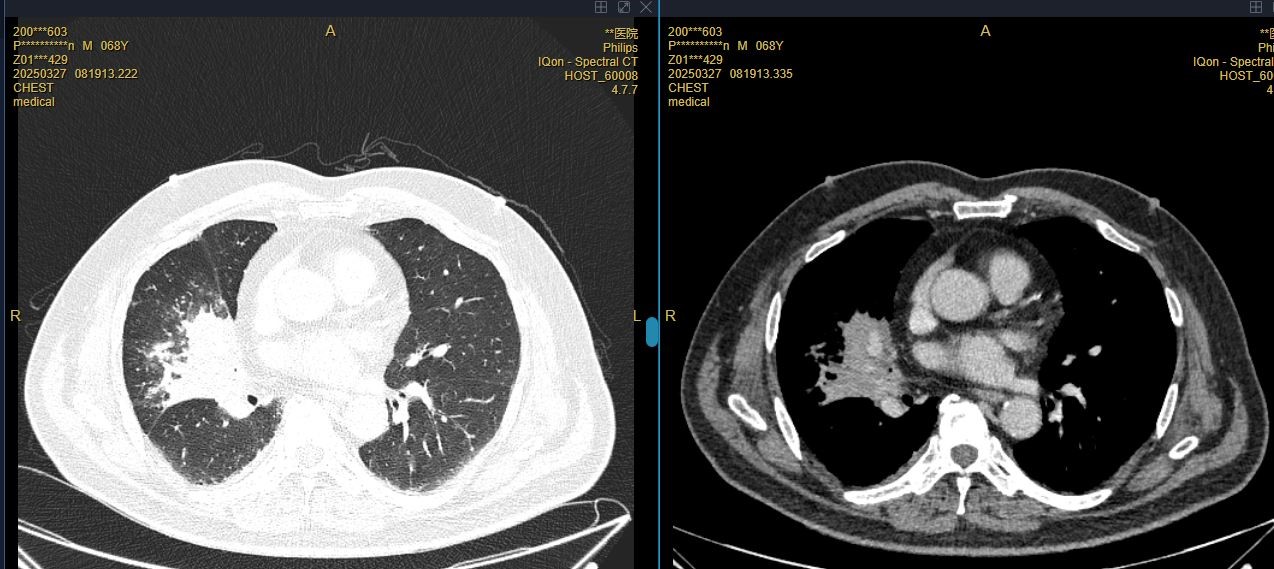

患者彭先生,因咳嗽一月余,加重伴发热2周入院。1月前出现咳嗽,较剧烈,伴有明显呛咳,患者未予重视;2周前咳嗽症状较前加重,伴咳较多黄浓痰,呛咳明显,咳嗽后胸闷气急较前加重,遂至外院就诊,查胸部CT示右肺中叶炎症,心脏增大。入院后余抗感染治疗后仍有反复发热,复查增强CT右肺中叶不张伴阻塞性肺炎,较前明显进展。328日在外院行支气管镜检查,见右肺中叶异物堵塞管腔,住院期间多次尝试取出异物,却因种种困难未能成功。回顾病史,患者不仅有脑梗塞、高血压等基础疾病,还曾经历颅脑外伤、腰椎手术、气管切开术,既往手术麻醉后出现谵妄,麻醉风险极高,为手术增添了重重阻碍。